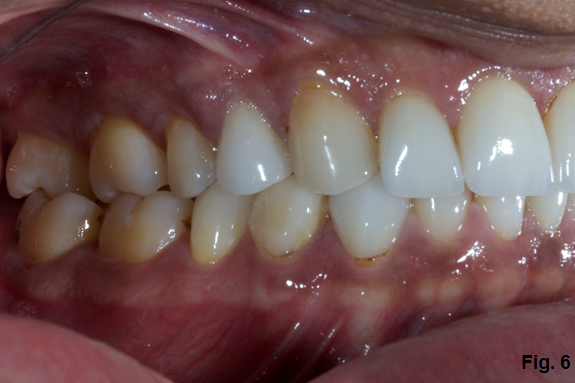

Orthognathic surgery is the least favorable option in this case. Although he has a transverse discrepancy and has end to end posterior occlusion, there are easier and less invasive ways to give him overjet. (Fig. 6)

Moving teeth would mean considering the labiolingual inclination of the upper anteriors, as well as the same position of the lowers. If we look at the angle of the upper incisor to the occlusal plane in Fig. 6, the inclination of the incisors could be increased slightly. In the lower arch, the lower anterior could be retracted slightly with some interproximal reduction and create the overjet needed to redo the case.